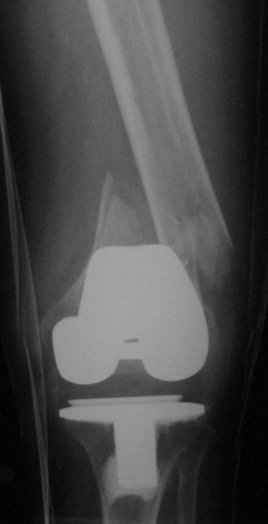

Go antegrade if you have an approriate implant available. Attached is a result of a similar fracture.